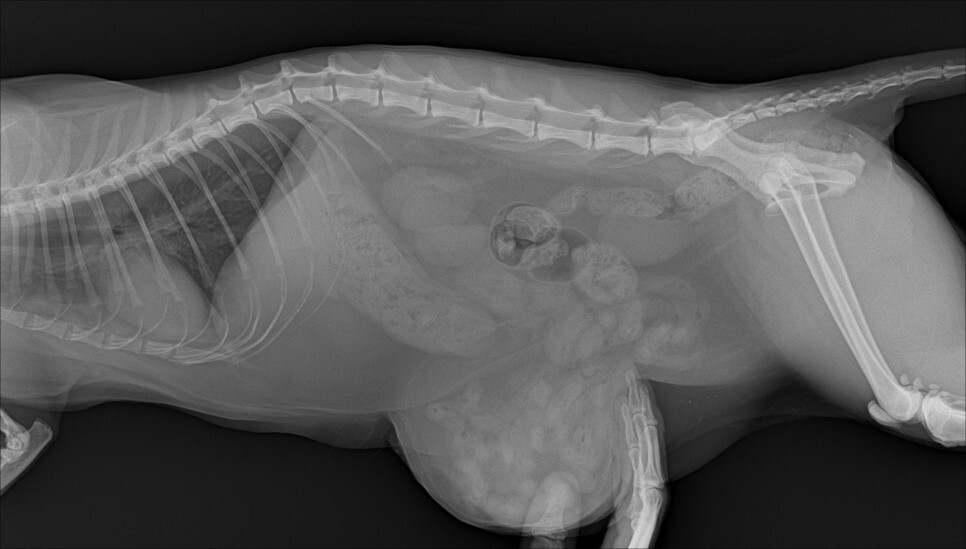

방사선 및 복부 초음파

이 아이의 경우 육안으로도 확연하게 확인이 가능할 정도로 서혜부쪽의 배가 볼록하게 나와있었습니다.

정확한 상태를 파악하기 위해서 엑스레이와 복부 초음파 검사를 하였습니다.

서혜부 탈장이 확인 되었고 수술을 진행하기로 결정하였습니다. 아이는 며칠 동안 입원하여 안정을 취하기로 하였습니다.